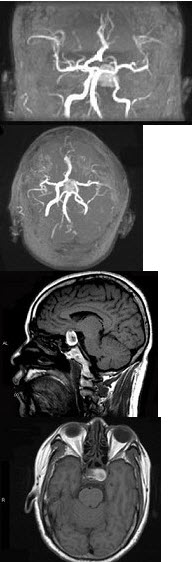

男性,55岁,头痛一年余,两个小时前突然出现剧烈头痛,MRI检查如图所示,最可能的诊断为( )

A:垂体瘤

B:脑膜瘤

C:颅咽管瘤

D:垂体瘤并卒中

E:动脉瘤